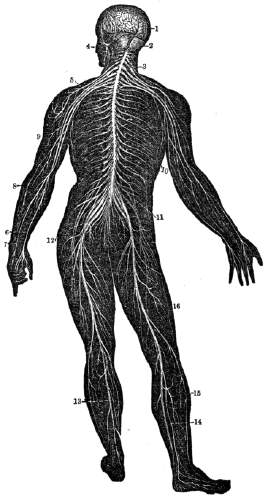

| 36. | Anatomy of the Nervous System, | 327 |

| 37. | Anatomy of the Nervous System, continued, | 340 |